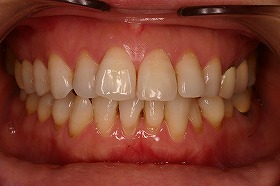

この患者様は、非抜歯で矯正治療を進めることができ、

治療後は上下の噛み合わせもよくなりました。